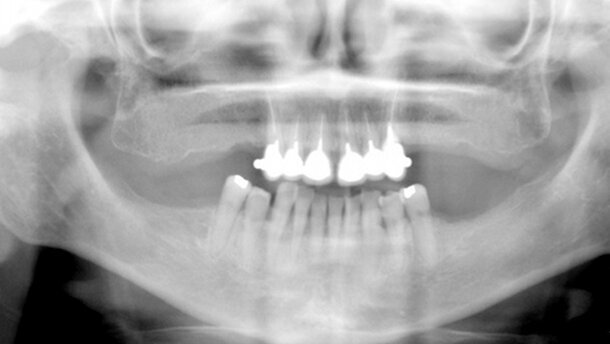

Imagen después de la retirada completa de la prótesis mixta en arcada superior de la paciente.

Acude a nuestra consulta una mujer de 57 años, tratada anteriormente mediante prótesis mixta en arcada superior, pero que tras 10 años empieza a presentar problemas, por lo que se decide como primera opción su retirada completa. (Fig.1).